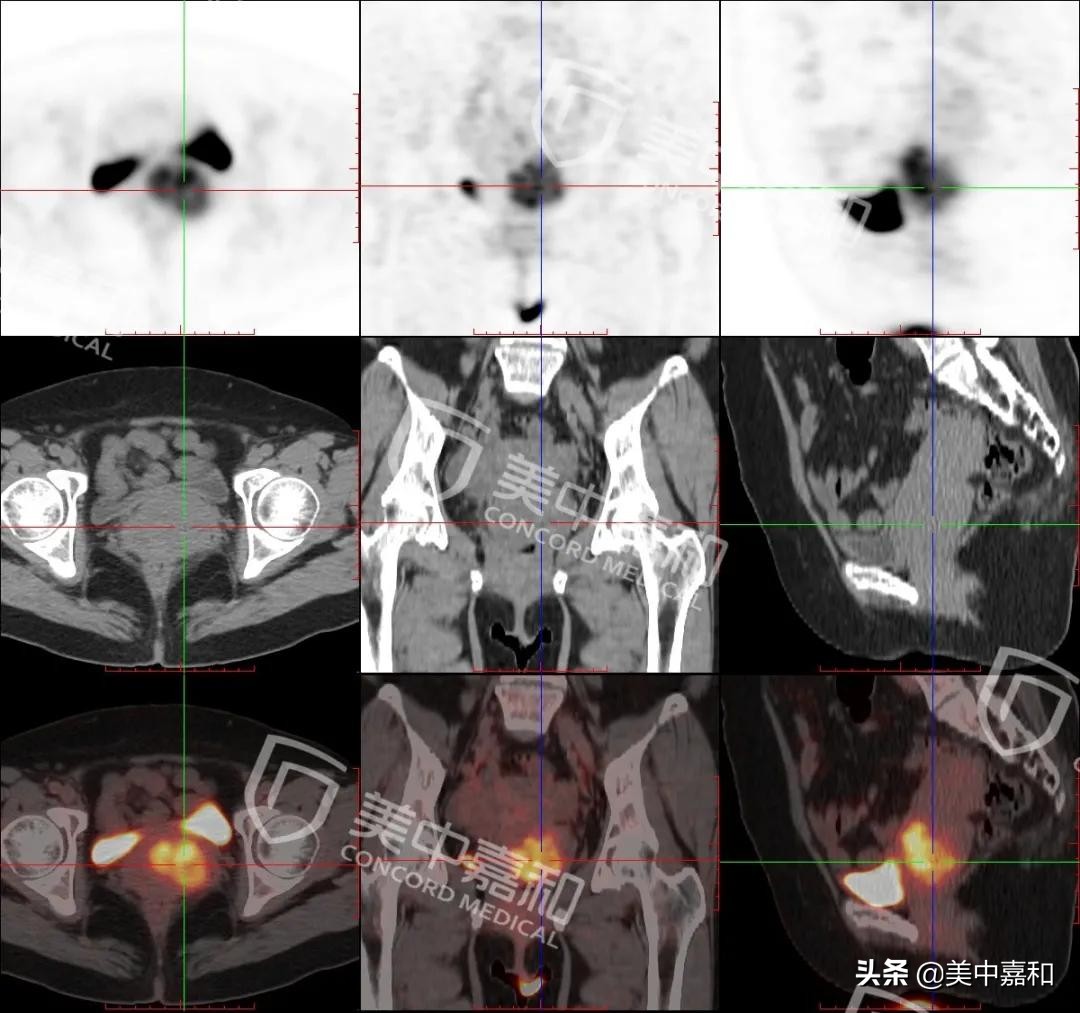

图1:宫颈壁不规则增厚伴软组织肿块,大小约4.2×2.8×4.4cm,FDG摄取增高,SUVmax 12.7